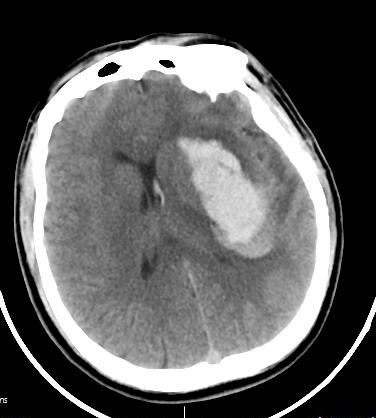

該名46歲男性患者,因“突發(fā)意識(shí)障礙伴惡心、嘔吐3小時(shí)”來(lái)醫(yī)院急診科就診,急診頭顱CT顯示“左側(cè)基底節(jié)區(qū)腦出血(出血量約43ml)”。急診完善頭頸部CTA排除腦血管畸形、動(dòng)脈瘤后,緊急收入神經(jīng)外科并即刻實(shí)施“神經(jīng)內(nèi)鏡下腦內(nèi)血腫清除術(shù)”,手術(shù)順利。術(shù)后患者神志清楚,頭部手術(shù)切口僅5cm左右。復(fù)查頭顱CT提示顱內(nèi)血腫大部分清除,經(jīng)術(shù)后積極對(duì)癥治療后痊愈出院。

圖1:術(shù)前頭顱CT提示左側(cè)基底節(jié)區(qū)腦出血(約43ml)